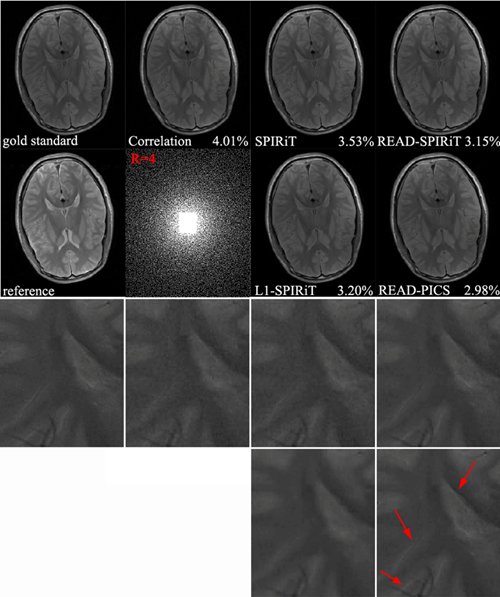

不同方法(其中READ-PICS是所提出的方法)4倍加速时的人脑磁共振图像重建结果

课题组彭玺博士的最新研究成果 Incorporating Reference in Parallel Imaging and Compressed Sensing MRM 接收。该研究提出广义级数模型、压缩感知、并行成像三者耦合的成像方法。经验证,该方法能够有效提高压缩感知理论所要求的信号稀疏性,改善并行成像系统的病态条件,具有更好的细节恢复和噪声抑制能力。